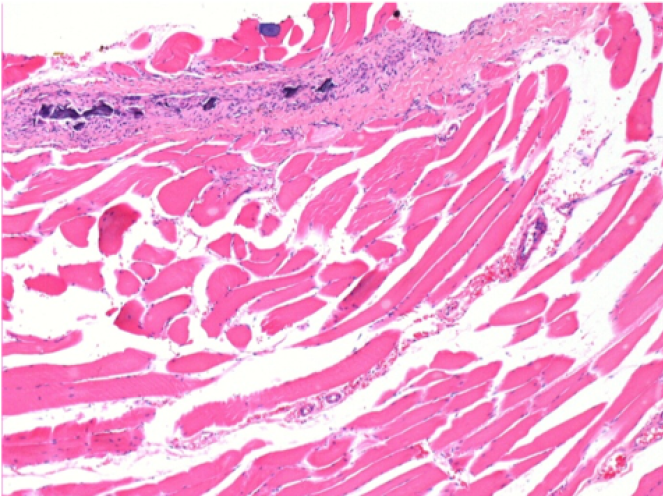

1 mes después de la inyección de Endopeel

1 mes después de la inyección de Endopeel 0,1 ml en el músculo pretibial derecho.

¡Lo que se ve en negro en las imágenes no es una necrosis como podrían imaginar algunos científicos!

De hecho, hay que tener en cuenta 4 conclusiones

- un artefacto de coloración

- una ausencia de necrosis

- una apoptosis

- un proceso biorregenerativo

L : Control-100xD30

R:100xD30

R :400xD30